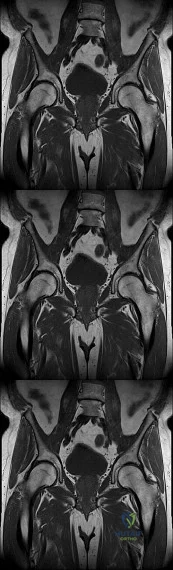

A 12-year-old obese boy presents with right hip pain and a limp. Radiographs confirm a stable severe right slipped capital femoral epiphysis (SCFE) with a Southwick slip angle of 65 degrees.

What is the strongest primary indication for prophylactic in situ pinning of the contralateral, asymptomatic hip?

A 12-year-old obese male presents with 3 weeks of left groin pain and a limp. Exam shows obligate external rotation with hip flexion. Radiographs confirm a stable left slipped capital femoral epiphysis (SCFE). Which of the following is the most appropriate absolute indication for prophylactic pinning of the contralateral asymptomatic hip?

A 12-year-old boy with a BMI of 32 presents with right knee pain and an obligate external rotation of the hip during passive flexion. Radiographs confirm a severe, stable slipped capital femoral epiphysis (SCFE). Prophylactic pinning of the contralateral, asymptomatic hip is most strongly indicated if the patient has a history of which of the following?